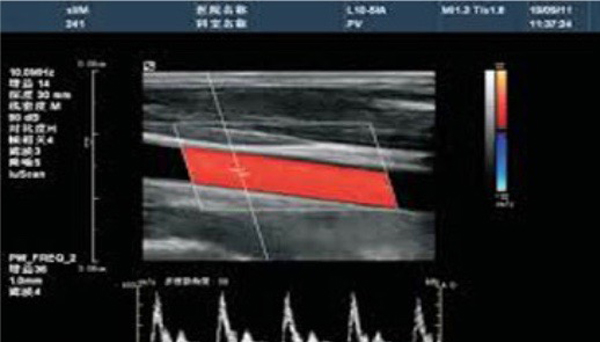

Colour Doppler sonography is an advanced ultrasound technique that combines traditional imaging with Doppler technology to visualize blood flow in the body. This non-invasive procedure provides real-time images of blood vessels and allows healthcare providers to assess the speed and direction of blood flow

It is commonly used to evaluate conditions related to the heart, vascular system, and various organs. The detailed analysis provided by Colour Doppler sonography is crucial for diagnosing vascular diseases, heart conditions, and monitoring blood flow in various clinical situations.